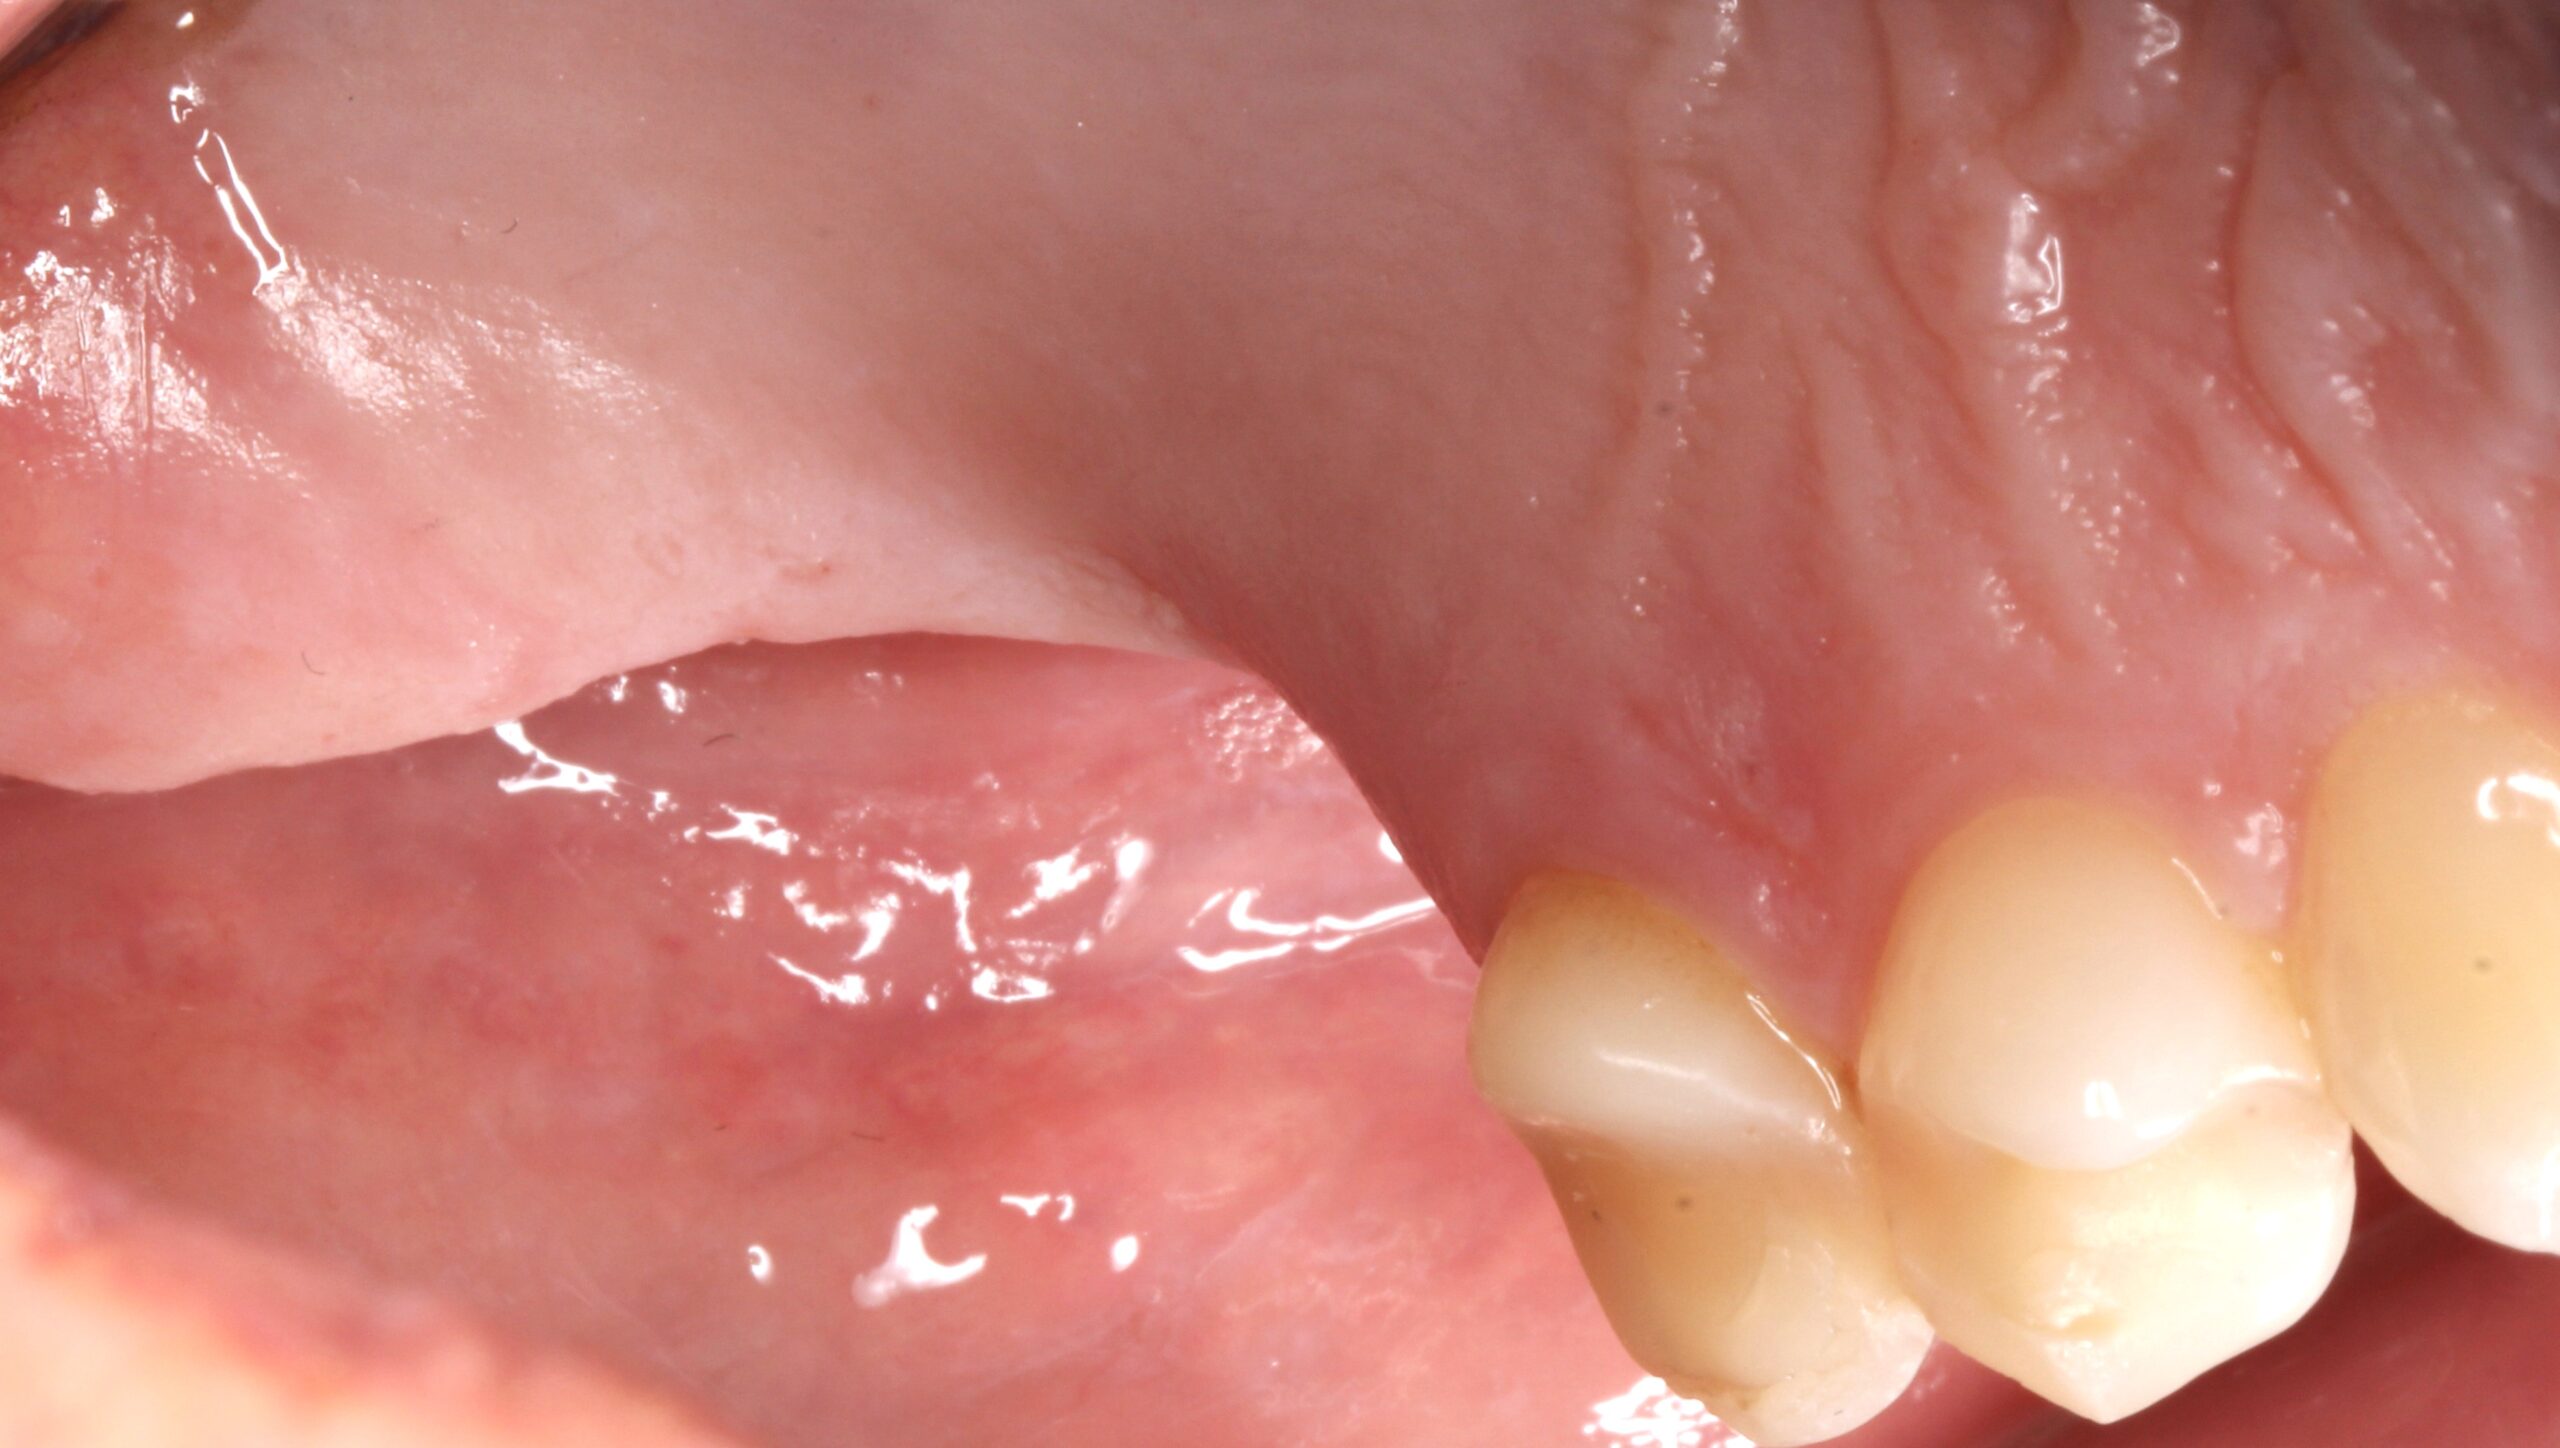

Figure 15.

2 months later a Free Gingival Graft was placed to reposition the mucogingival line.